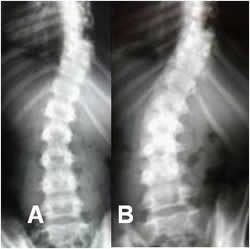

Fig 39. Progresión.

A y B: Rx AP. Escoliosis dorsolumbar derecha que ha progresado, después de 2 años de seguimiento.